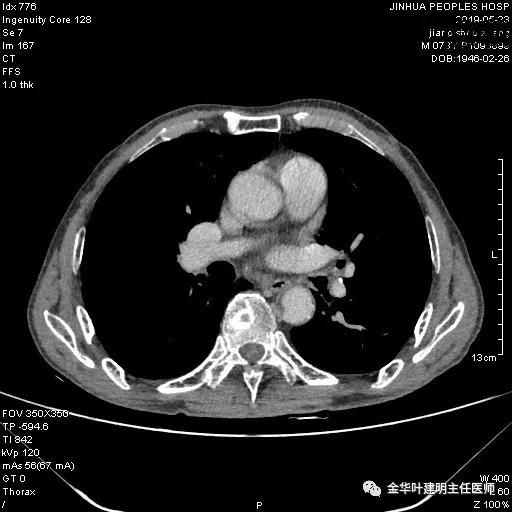

患者,男性,73岁,金华人。因“咳嗽咳痰伴胸闷2月,检查确诊左肺癌1周”入院。气管镜: 气管支气管内较多脓性分泌物,左肺上叶前段管腔新生物,局部活检、毛刷。气管镜病理:(左肺活检)鳞癌。阅胸部CT见左上叶开口处新生物,考虑需左上叶袖式切除及淋巴结清扫。具体CT表现如下:

术前检查冠脉CT示:左冠前降支近段多发钙化斑块伴管腔重度狭窄(约85%),建议DSA检查。但追问病史以往平时无胸痛或胸闷症状,运动试验提示可疑阳性(上斜型压低),活动后胸闷气闭症状不明显,既往否认高血压、糖尿病。所以经过心内科会诊讨论,认为还是可以进行手术。术前冠状动脉CT示: